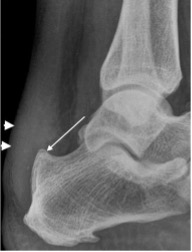

Haglund Deformity

- Prominent bony protrusion of posterior superior calcaneal tuberosity

- Soft tissue swelling of distal Achilles tendinopathy and retrocalcaneal bursitis resulting in Haglund’s syndrome

- Problems with footwear

Haglund’s deformity (thin arrow) with soft tissue swelling (bold arrowheads)